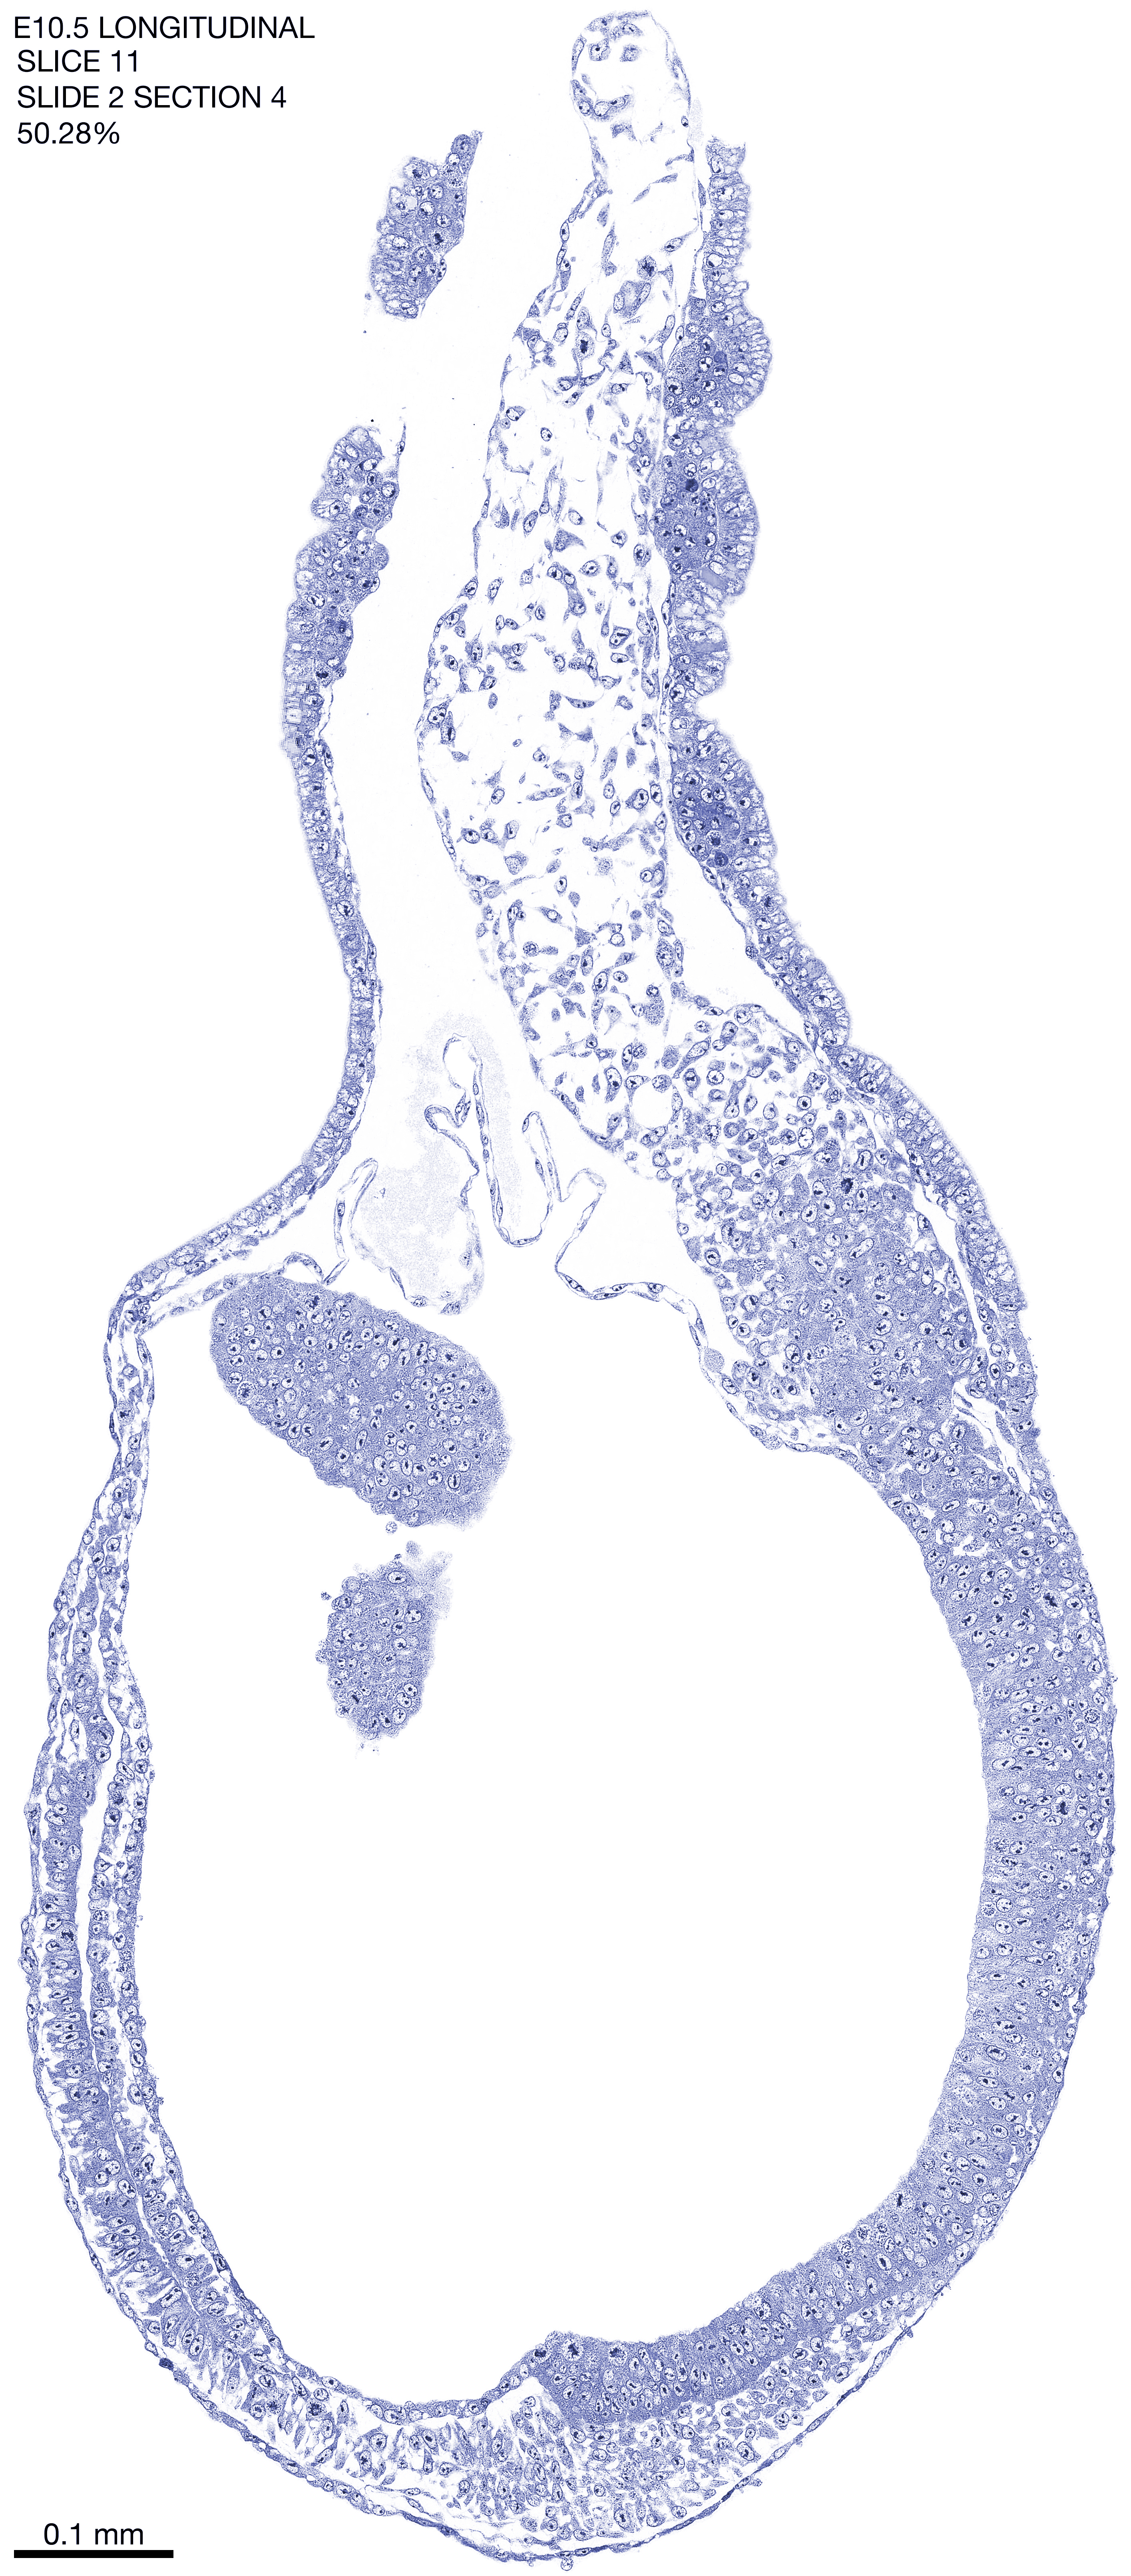

E10.5 Longitudianal Archive This page contains jpg files of ALL SLICES (each 3µm thick) that were scanned of the E10.5 longitudinally cut specimen. Download: Large | High Res Download: Large | High Res Download: Large | High Res Download: Large | High Res Download: Large | High Res Download: Large | High Res Download: Large | High Res Download: Large | High Res Download: Large | High Res Download: Large | High Res Download: Large | High Res Download: Large | High Res Download: Large | High Res Download: Large | High Res Download: Large | High Res Download: Large | High Res Download: Large | High Res Download: Large | High Res Download: Large | High Res Download: Large | High Res Download: Large | High Res Download: Large | High Res Download: Large | High Res Download: Large | High Res Download: Large | High Res Download: Large | High Res Download: Large | High Res Download: Large | High Res Download: Large | High Res Download: Large | High Res Download: Large | High Res Download: Large | High Res Download: Large | High Res Download: Large | High Res Download: Large | High Res Download: Large | High Res Download: Large | High Res Download: Large | High Res Download: Large | High Res Download: Large | High Res Download: Large | High Res Download: Large | High Res Download: Large | High Res Download: Large | High Res Download: Large | High Res Download: Large | High Res Download: Large | High Res Download: Large | High Res Download: Large | High Res Download: Large | High Res Download: Large | High Res Download: Large | High Res Download: Large | High Res Download: Large | High Res Download: Large | High Res Download: Large | High Res Download: Large | High Res Download: Large | High Res